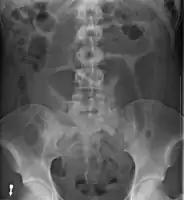

- Abdominal x-ray – tire-like shadow arising from right iliac fossa and passing to left

An x-ray of a person with a small bowel volvulus.